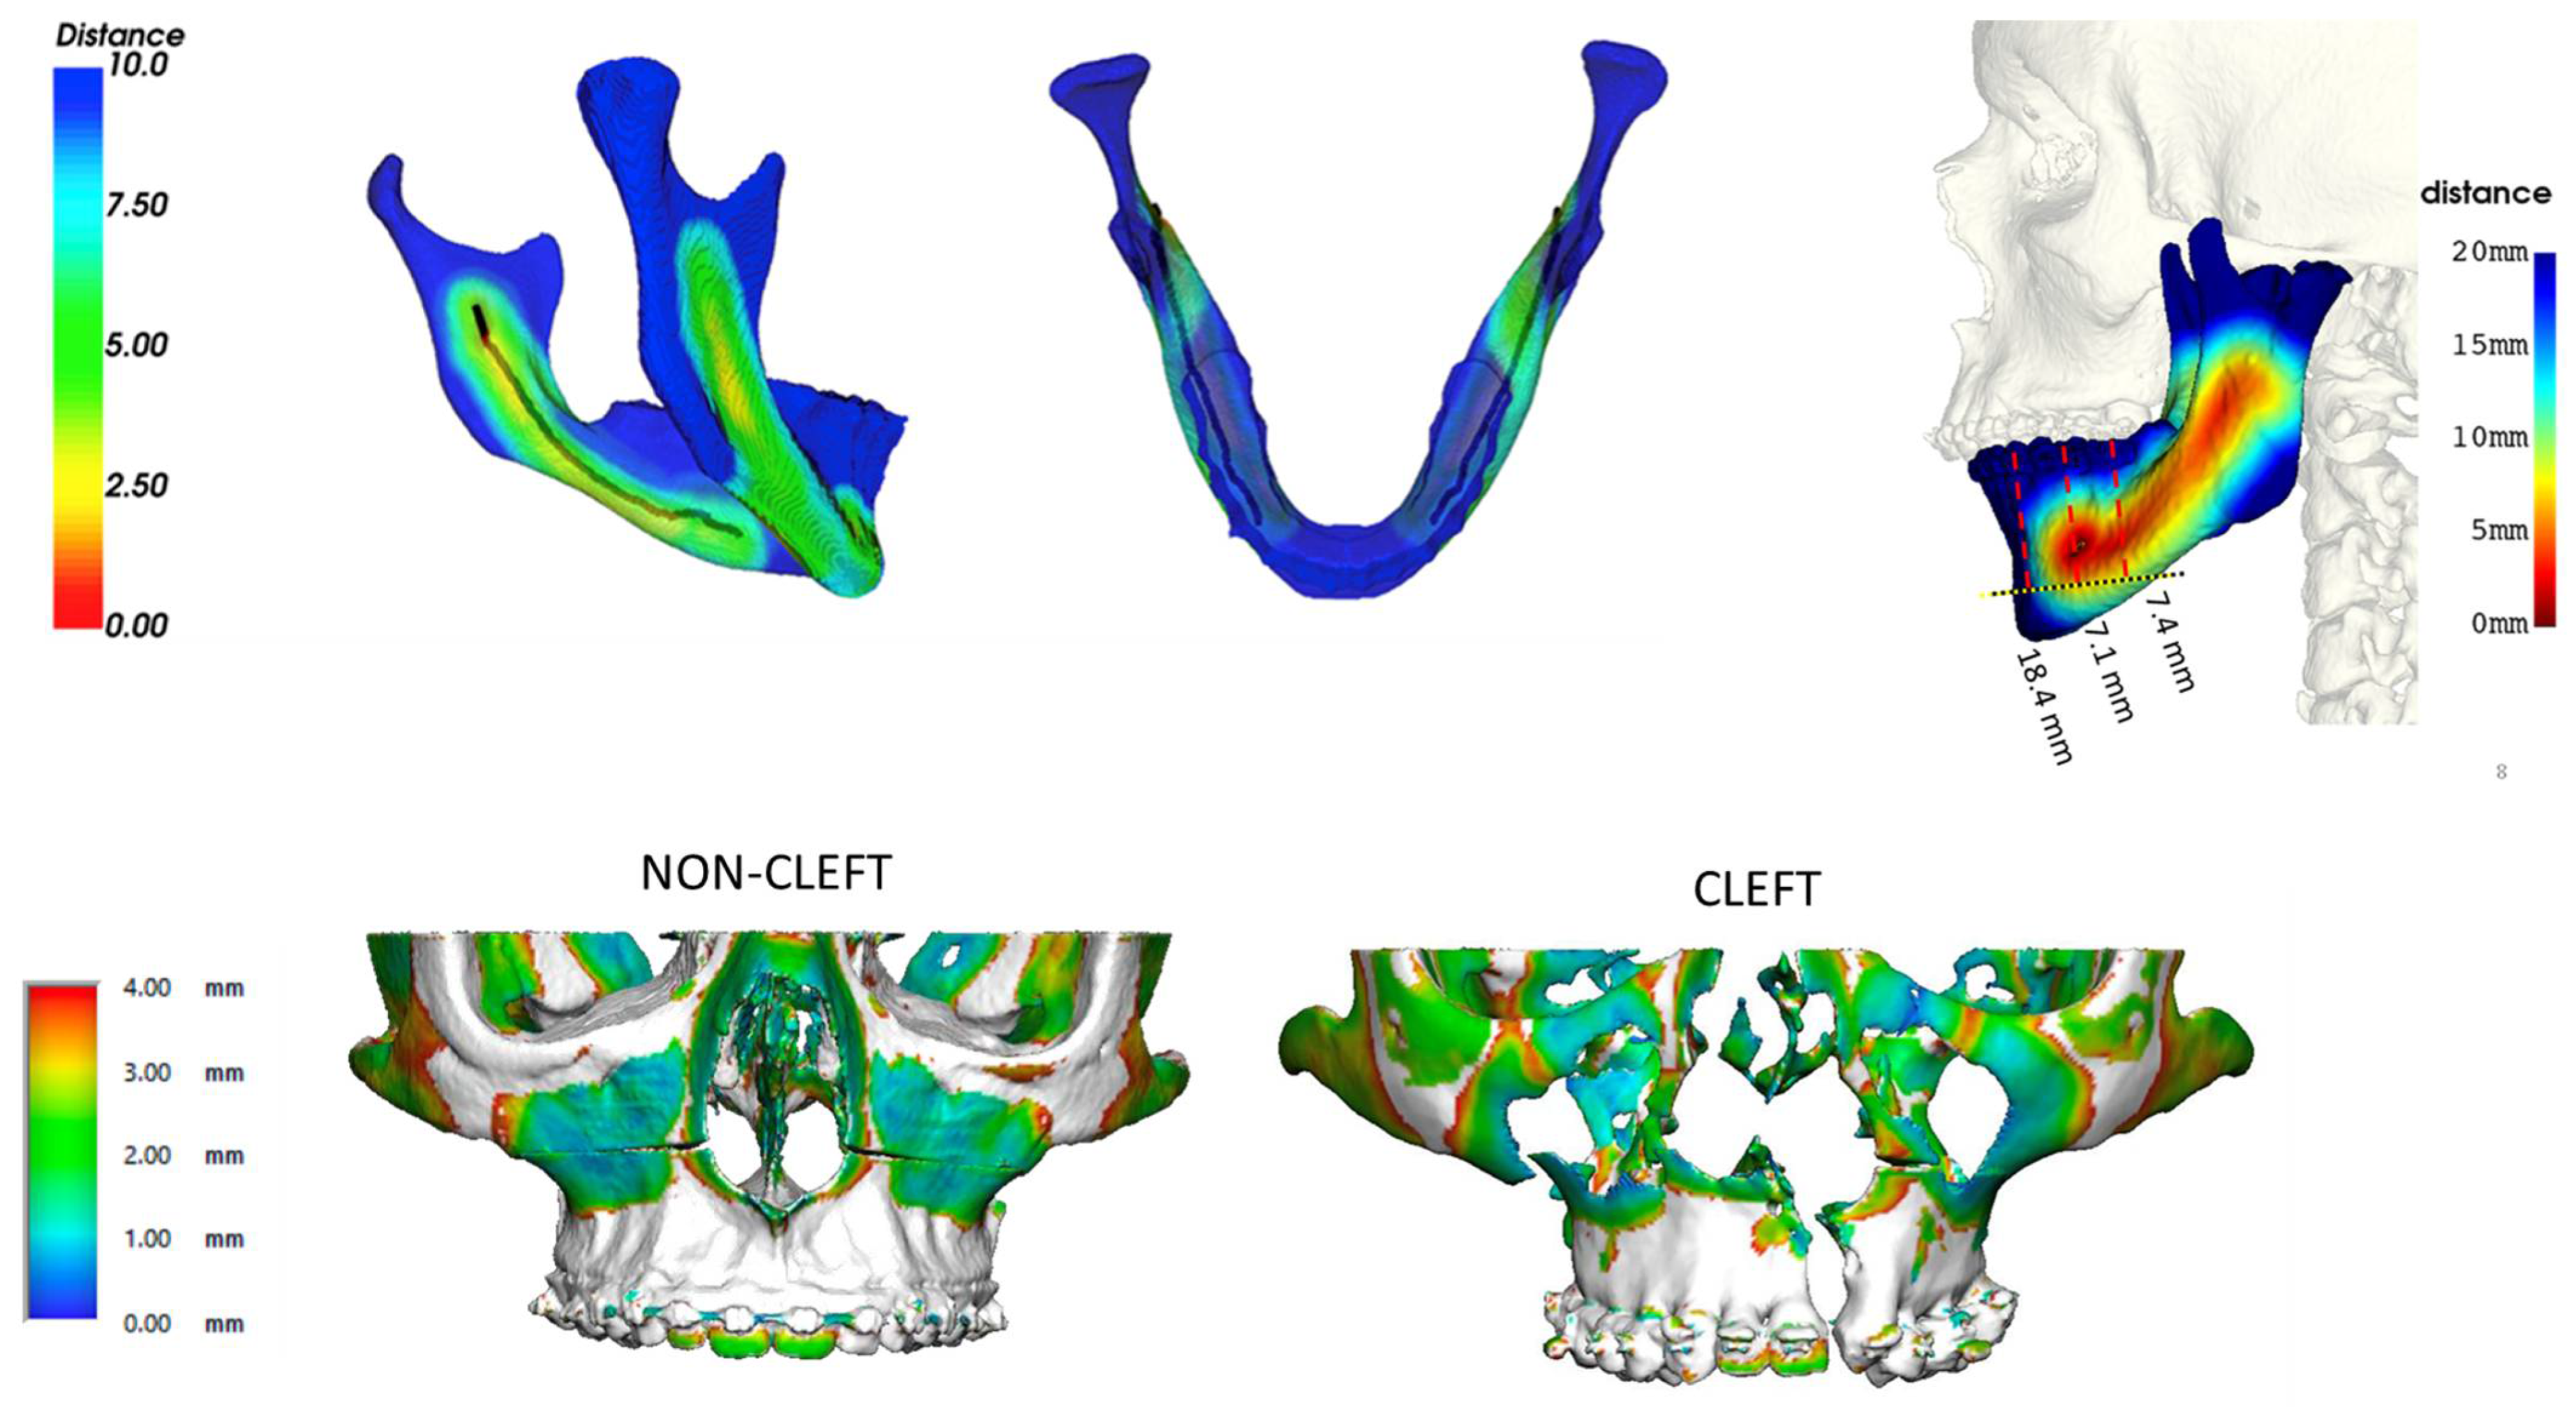

2. Advances in Surgical Planning

5. In-House Computer-Assisted Surgical Planning

- Ettinger, R.E.; Mercan, E.; Podolsky, D.; Susarla, S.M. Defining the Safe Zone for the Low Medial Horizontal Cut in the Sagittal Split Osteotomy. J. Oral Maxillofac. Surg. 2022, 80, 822–826. [Google Scholar] [CrossRef]